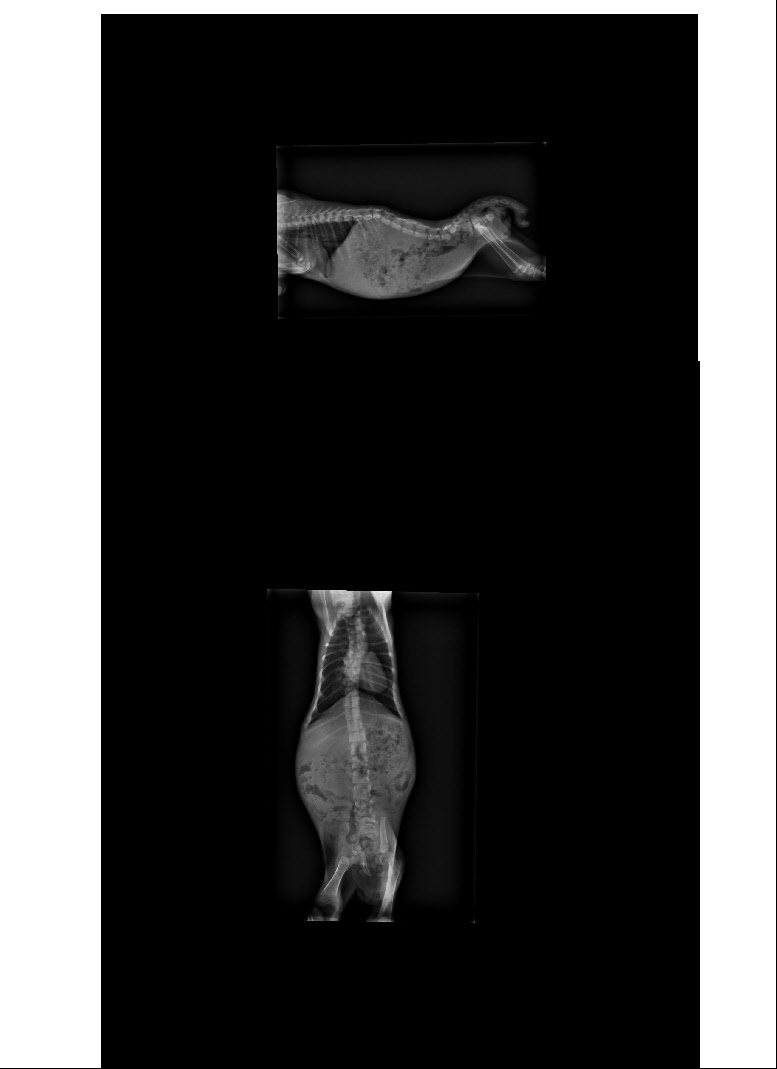

- 編號: 2878

主題: 網友通報癱瘓小虎斑 申請者姓名: Sally Chang 花色: 申請日期: 2013-08-25 02:48:56 申請者部落格: 申請者臉書網址: 所在縣市/合作醫院: 高雄市/恩澤動物醫院 治療費用: 7600元 需求人數: 9人 已結案 (2013-09-03 16:21:11) 報名人員: 戴戴(已付款)、Bella(已付款)、Jillfly(已付款)、Liwing Lin(已付款)、Guan-Yi Li(已付款)、Yuyu Amy Wu(已付款)、Jessicaer Chien(已付款)、Elva Chen(已付款)、SweetTpg(已付款)、 候補人員: 動物病情說明: https://www.facebook.com/photo.php?fbid=209898069169658&set=o.116487248386284&type=1&theater

發現脊椎斷了兩處,

且後肢是沒有知覺的...

也無法自行排便排尿,

須仰賴人工協助。

在學理上,

癱瘓的可能性真的很高....

1.口服藥治療1wk 500

2.X-ray 400*2

3.血液檢查 1200+600(FeLV/FIV)+600(FPV)

4.點滴抗生素治療 600*6

5.住院費用 400*8

6.除蚤 250 (不折扣)

total 10500*0.7+250=7600